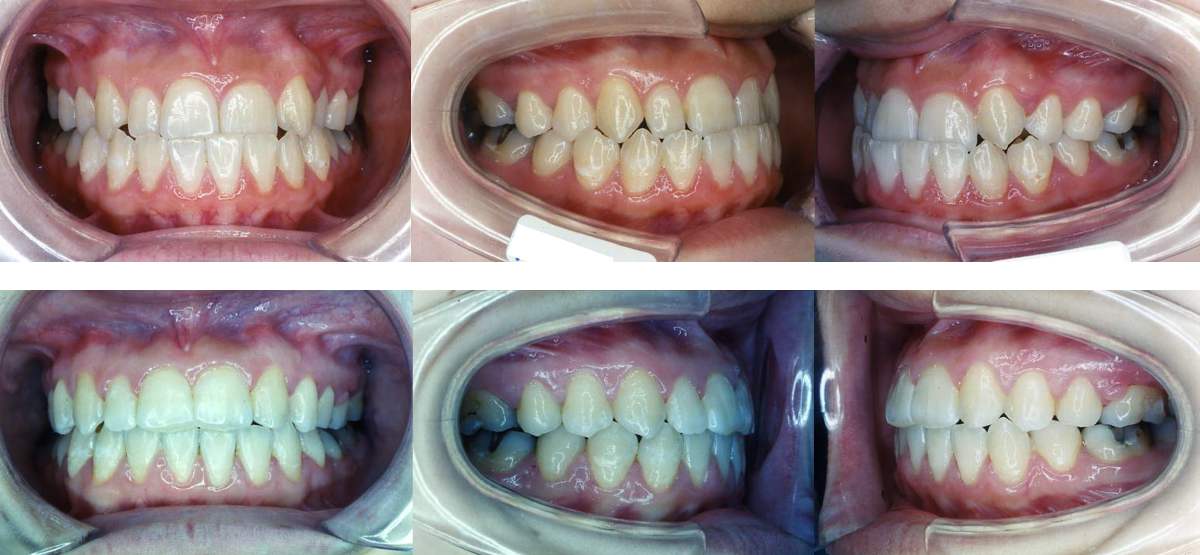

④受け口(下顎前突)の矯正治療例(10代女性・治療期間2年1か月)

| 年齢・性別 | 10代女性 |

| 治療期間 | 2年1か月 |

| 抜歯 | 下1本(小臼歯) |

| 治療費 | 50万円(調整費、保定費まで含む総額制) |

| 備考 | インビザライン |

| リスク・副作用 | 痛み・治療後の後戻り・歯根吸収・歯髄壊死・歯肉退縮 |